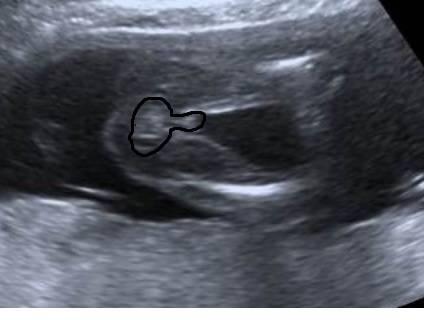

Hä? Ich sehe da eindeutig einen großen Hodensack, zwei Hoden und den Schniedel wo soll da ein Mädchen sein

Hier nachgezeichnet, nicht professionell, aber das was ich sehe

Bild zu